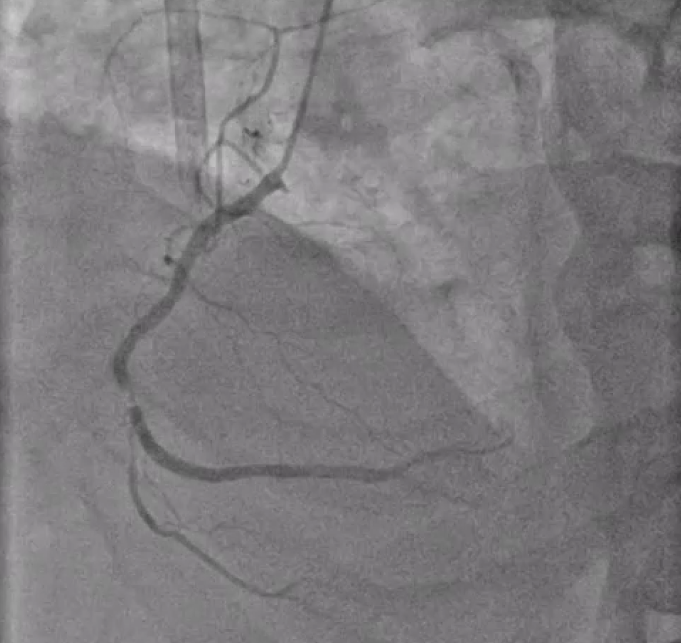

Angiography showed triple vessel disease involving LM-LAD-LCx bifurcation with eccentric calcium nodule in the ostial LCx. Severe calcification was noted throughout the proximal to mid LAD with some focal severe stenosis. RCA showed one area of severe focal stenosis.

RCA.mp4